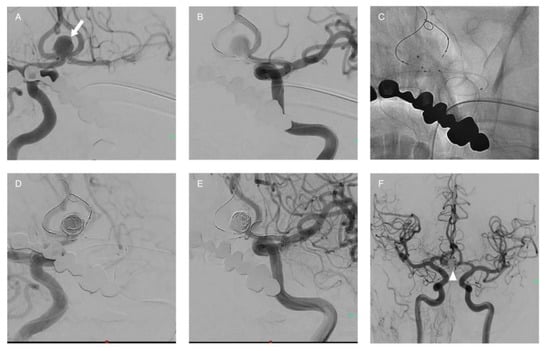

3.3. Stent-Assisted Coiling (SAC)

- Henkes, H.; Bose, A.; Felber, S.; Miloslavski, E.; Berg-Dammer, E.; Kühne, D. Endovascular Coil Occlusion of Intracranial Aneurysms Assisted by a Novel Self-Expandable Nitinol Microstent (Neuroform). Interv. Neuroradiol. 2002, 8, 107–119. [Google Scholar] [CrossRef]

- Higashida, R.T.; Halbach, V.V.; Dowd, C.F.; Juravsky, L.; Meagher, S. Initial Clinical Experience with a New Self-Expanding Nitinol Stent for the Treatment of Intracranial Cerebral Aneurysms: The Cordis Enterprise Stent. Am. J. Neuroradiol. 2005, 26, 1751–1756. [Google Scholar]

- Wang, F.; Chen, X.; Wang, Y.; Bai, P.; Wang, H.Z.; Sun, T.; Yu, H.L. Stent-Assisted Coiling and Balloon-Assisted Coiling in the Management of Intracranial Aneurysms: A Systematic Review & Meta-Analysis. J. Neurol. Sci. 2016, 364, 160–166. [Google Scholar] [CrossRef] [PubMed]

- Mine, B.; Bonnet, T.; Vazquez-Suarez, J.C.; Iosif, C.; Lubicz, B. Comparison of Stents Used for Endovascular Treatment of Intracranial Aneurysms. Expert Rev. Med. Devices 2018, 15, 793–805. [Google Scholar] [CrossRef] [PubMed]